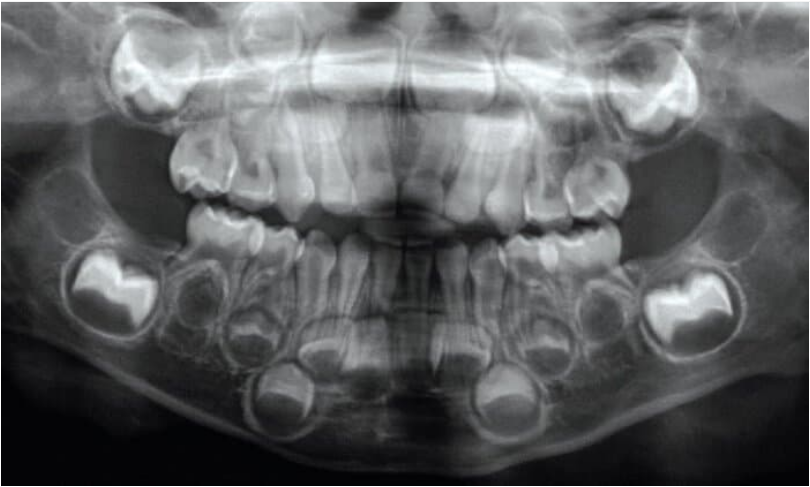

Baby teeth begin calcifying when we are still in the uterus, as does our first permanent molar. These teeth preserve lines that indicate the temporary position of enamel- and dentine-forming cells during birth. Scientists discovered these neonatal lines by examining hundreds of baby teeth from human children, finding dark, accentuated lines in a similar position in most teeth. Dental researcher Isaac Schour was the first to suggest that this microscopic disruption is caused by the physiological transition of birth. Others have since counted subsequent daily growth lines in young individuals, finding close agreement with their age and confirming that this line is indeed formed at birth.

Under the microscope one can often see that enamel prisms deviate slightly from their straight course as they pass through the neonatal line. The adjacent enamel also shows a change in mineralization, producing a darkly contrasted line. Some hypothesize that these lines appear in infants’ teeth because of changing calcium levels during or just after birth.

Being able to find dental birth certificates and subsequent physiological disruptions etched into teeth has opened up new possibilities for understanding the development of our ancestors and close evolutionary relatives. Neonatal lines allow precise age estimates for young individuals in the fossil record though counts of the microscopic daily growth between birth and death, when tooth formation ceases prematurely. This has helped to confirm that earlier hominins grew and erupted their teeth more quickly than humans living today — likely maturing earlier than modern children. The presence of postnatal accentuated lines has also allowed us to explore the first few years of Neanderthal childhoods on a weekly basis — showing greater disruptions during wintertime, including a likely illness during the height of winter. These are just a few of many tales that we can tease out of those who are brave enough to bare their teeth.